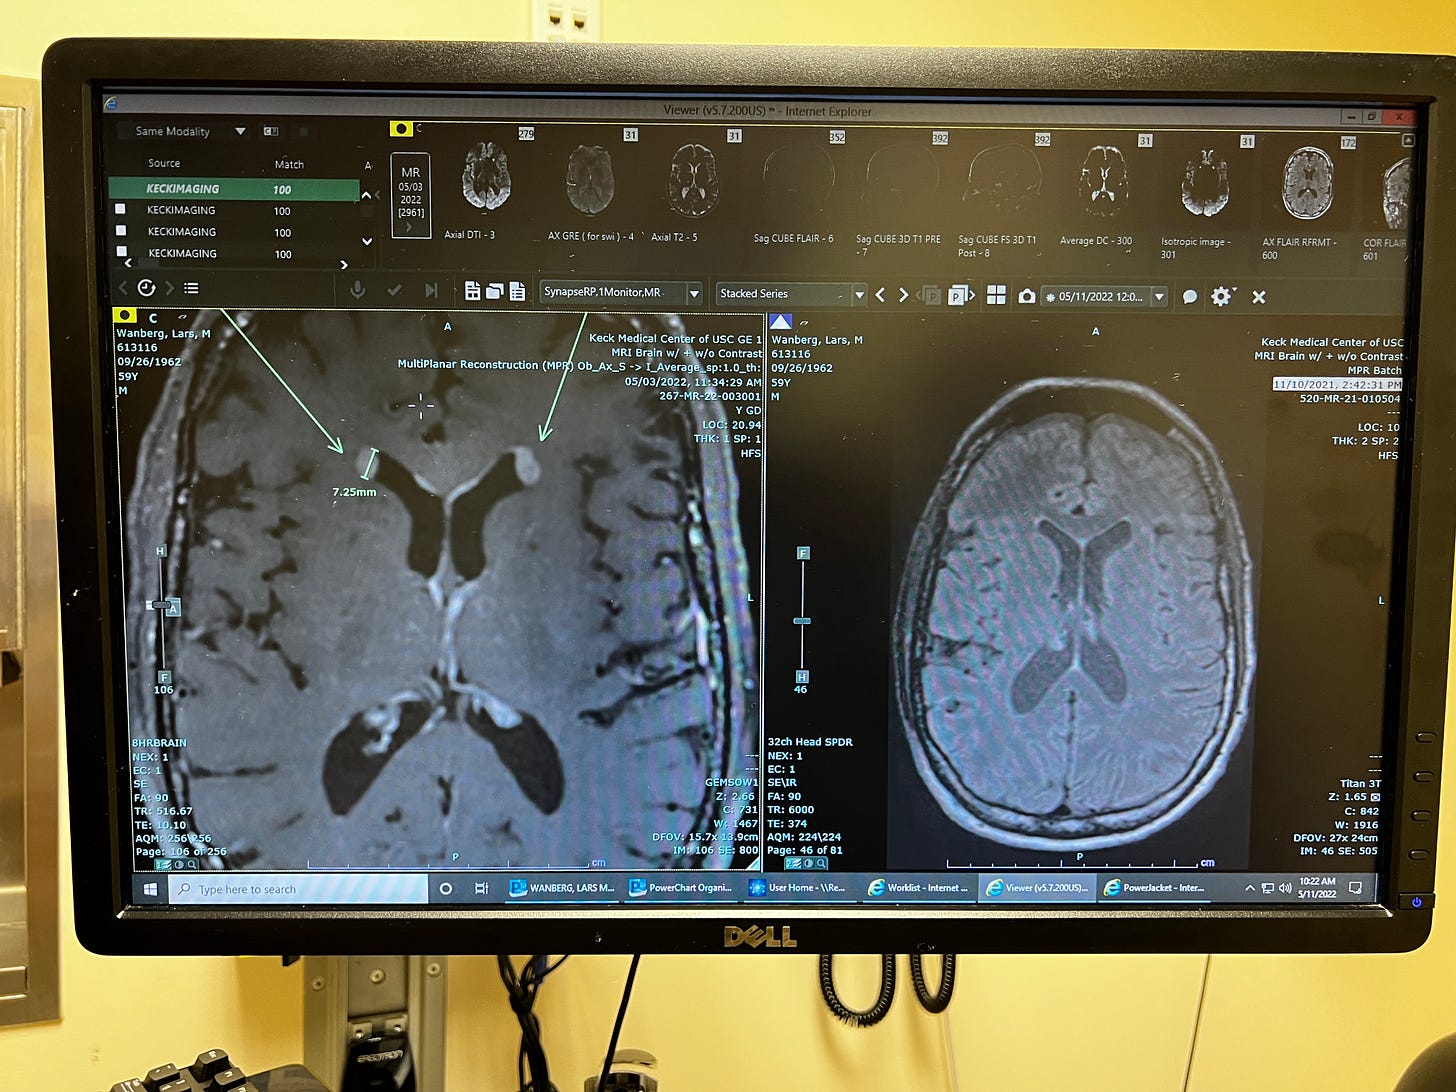

When tumors were found in my brain I learned about cerebrospinal fluid. We have up to 150ml of fluid in our cerebrospinal system that moves through our brain and spinal cord at any given time. It turns over 4 times a day connecting neurotransmitters and signaling molecules. It also acts as a shock absorber between our brain and skull that protects our brain from injury. If the brain is not made buoyant by this fluid, gravity would make the weight of our brains too much for our spine to carry. The CSF is produced in the lateral ventricle, one of four deep caverns of space in the brain that flows one to the other, all the way down the spinal cord. If a tumor blocks the flow of fluid it builds up (water on the brain) and needs an escape valve. When it happened to me a neurosurgeon drilled a hole in my skull and inserted a shunt into my lateral ventricle to relieve the pressure. When the fluid is flowing normally it washes the brain and spine with a clear fluid rich in proteins, ions, lipids, hormones, cholesterol, glucose, and many other molecules.